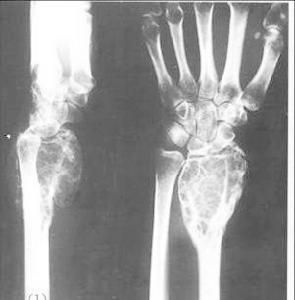

X線徵象:發生於指(趾)骨時,一般呈中心位。可見邊緣清晰,整齊的囊狀透明陰影,受累骨皮質膨脹變薄,在透明陰影內,可見散在的砂粒樣緻密點,這是軟骨瘤主要的X線征。發生於掌(蹠)骨者,有時腫瘤陰影較大,常偏於骨端,骨皮質的膨脹亦較顯著,但均無骨膜反應。發生於四肢長骨的病例,腫瘤的陰影廣泛。當腫瘤惡變時,則可見骨皮質破壞及骨膜反應